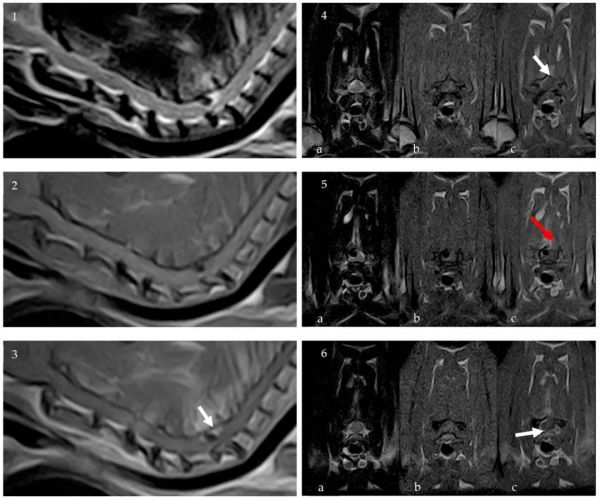

CT扫描后立即进行了颈胸椎的0.32 T MRI检查。证实在T1W和T2W序列上存在均匀的低密度物质,符合部分矿化的硬膜外病变。病变呈卵圆形,边缘规则,位于C6-C7椎间隙,在脊髓右侧和背侧,大小约2.5×2×4 mm。对脊髓造成了严重压迫,估计约占横截面积的50%。没有骨折、脱位或外伤迹象。对比后显示病变周围脊髓脑膜增强,右侧椎旁肌肉轻度增强,尤其是右侧C6-C7关节面关节周围突出(下图)。

↑ MRI成像:颈椎矢状位T2W(1)、矢状位T1W(2)和对比后T1W(3)图像。C6 椎体水平[(4a) T2W、(4b) T1W、(4c)对比后T1W]、C6-C7椎间隙水平[(5a) T2W、(5b) T1W、(5c)对比后T1W]和C7椎体水平[(6a) T2W、(6b) T1W、(6c)对比后T1W]图像。证实T1W和T2W序列上存在均匀低密度物质,符合硬膜外部分矿化。对比后序列显示病变周围脊髓脑膜增强(白色箭头),右侧椎旁肌肉轻度增强(红色箭头)。